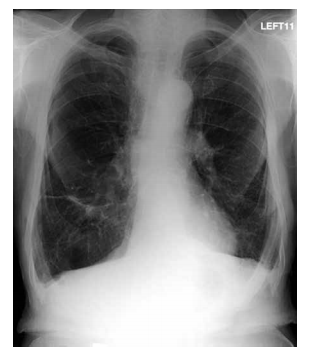

Homem, 46 anos, com antecedente de infarto agudo do miocárdio, é portador de miocardiopatia isquêmica e insuficiência cardíaca. Atualmente recebe tratamento otimizado para insuficiência cardíaca, no entanto permanece em classe funcional III (NYHA). O ecocardiograma mostra diâmetro diastólico do ventrículo esquerdo = 72 mm e fração de ejeção do VE = 34%. Holter de 24 horas: extrassístoles ventriculares frequentes, quatro episódios de taquicardia ventricular não sustentada e um episódio de taquicardia ventricular sustentada com 1 minuto de duração. O eletrocardiograma está ilustrado a seguir.

Assinale a alternativa correta em relação à redução de morbimortalidade do paciente em questão.